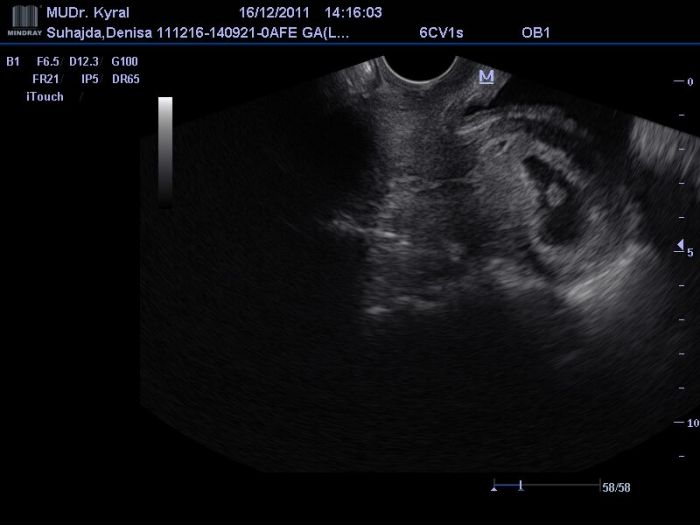

Ahoj holky, všecky Vás moc zdravím a držim palečky, at nám to vše dobře dopadne a miminko je zdravé. Mám za sebou kontrolu u dr., jsem štastná miminko jsem viděla a slyšela i srdíčko, ale jen trošku, jsem v 6tt+4, tak prý je to na hraně slyšitelnosti. Konečně mám svou první fotku miminka, krásný vánoční dárek. Jsem opravdu moc a moc štastná...